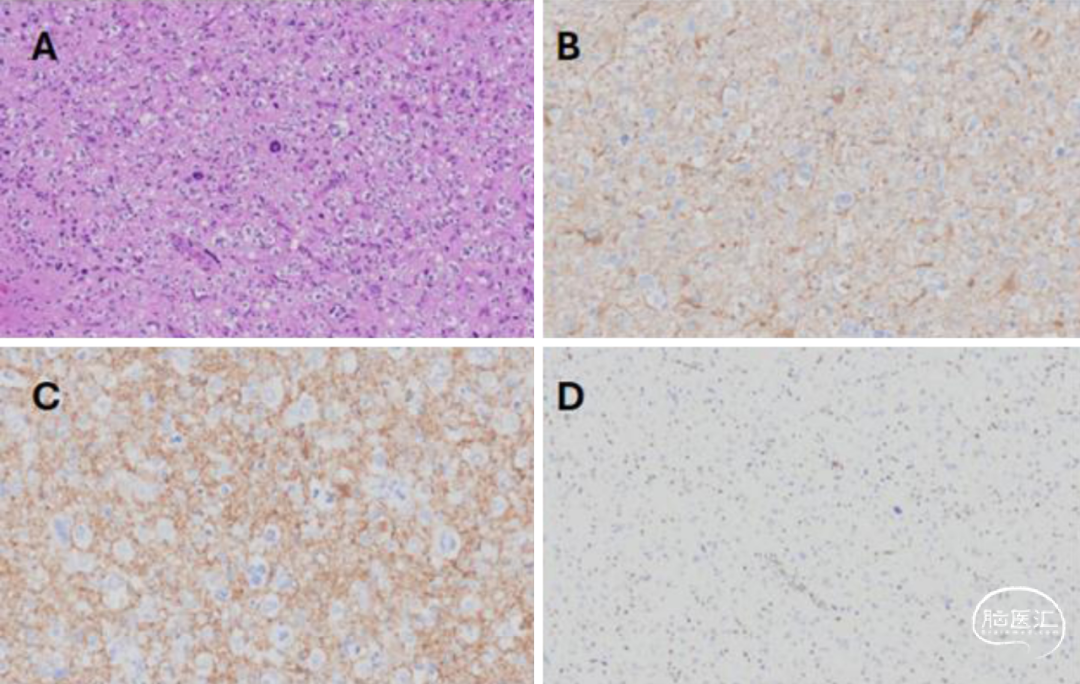

2.术后病理:总体而言(图2),与具有少突胶质瘤样特点及核簇的弥漫性胶质神经元肿瘤(DGONC)相符,但美国国立卫生研究院进行的DNA甲基化分析未能匹配到任何已知的肿瘤亚型,最终诊断为弥漫性胶质瘤/胶质神经元肿瘤,未明确WHO分级。

图2. A:肿瘤由具有核周空晕的细胞组成,其中散布着肿瘤巨细胞;B:肿瘤细胞中胶质纤维酸性蛋白(GFAP)表达呈不同程度的阳性;C:部分肿瘤细胞呈现神经元形态,并且突触素染色呈阳性;D:肿瘤细胞显示MSH2表达缺失。

3.分子检测:Caris检测结果显示肿瘤存在高度微卫星不稳定性(MSI)和较高的肿瘤突变负荷。肿瘤细胞中MSH2表达缺失(图2D),提示存在错配修复缺陷。生殖系检测确认了MSH2突变的存在,与林奇综合征(LS)的诊断一致,因此该肿瘤被分类为错配修复缺陷的弥漫性胶质/胶质神经元肿瘤,尚未明确分类。